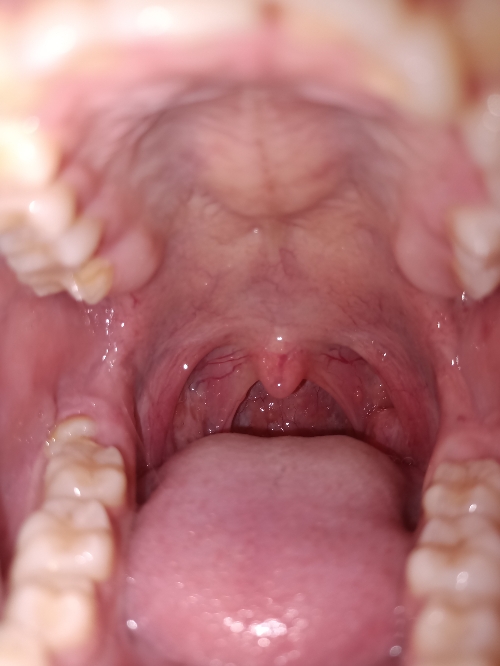

Họng e có hơi viêm 1 chút